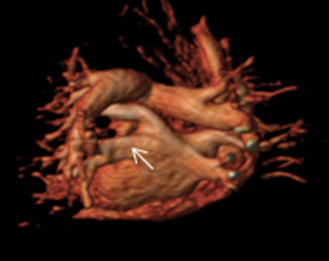

3. Strukturelle Herzerkankungen (SHD) und angeborene Herzfehler

Mit Hilfe von planimetrischen Verfahren (Bestimmung der Klappenöffnungsfläche) sowie Phasen-Kontrast-Sequenzen kann sowohl die morphologische als auch funktionelle Quantifizierung von Herzklappenerkrankungen (z.B. Aortenklappen-Erkrankungen) erfolgen. Nach erfolgter minimalinvasiver Klappenimplantation kann die Funktion der Herzklappe sowie die Struktur des Myokards verlaufsbeurteilt werden.

Die 3-dimensionale Darstellung des Herzens und der großen abgehenden Gefäße ermöglicht es dem CMR, komplexe anatomische Strukturen bei Patienten mit angeborenen Herzfehlern darzustellen. So kann in fast allen Fällen ein umfassender Aufschluss über anatomische und funktionelle Zusammenhänge gegeben werden. So stellt grade bei vielen angeborenen komplexen Herzfehlern das CMR den Goldstandard in der Diagnostik dar. Zudem sind Patienten mit angeborenen Herzfehlern häufig auf lebenslange genaue Verlaufskontrollen angewiesen. Diese können beliebig oft und strahlungsfrei mit dem CMR durchgeführt werden.

Vor und nach Aortenklappenersatz Darstellung großer Gefäße